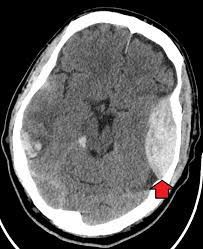

An epidural hematoma (EDH) is a collection of blood that forms between your skull and the dura mater, the outermost protective membrane covering your brain. The cause is usually an artery that gets torn by a skull fracture. Symptoms include severe headache and loss of consciousness.